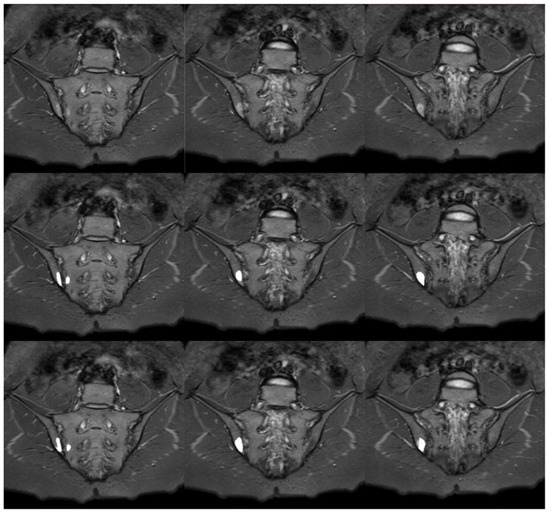

3.4. Manual and Automatic Segmentation of BME

The sample comparison of the performance of manual and automatic segmentations of BME is presented in Figure 8. The results of assessing the compatibility of manual and automatic BME segmentations with the visual scale described previously are provided in Table 4. Differences between the groups were checked using Kruskal–Wallis H test, which resulted in not being statistically significant, H(3) = 1.125, p = 0.7710. This outcome implies no difference in the algorithm’s performance in BME segmentation in relationship to the deviation angle. Due to the limitations of the SPARCC scale, the number of examinations which points were awarded (SPARCC > 0, n = 68) differs from the number of examinations with BME recognized when preparing manual segmentations (n = 83).

Figure 8.

Sample slices with inflammatory lesions (SPARCC = 17): STIR sequence in the upper row, manual segmentation in the middle row and automated segmentation in the lower row.

Table 5 summarizes the results of the visual scoring scale with the division of each joint into quadrants. These results suggest that the algorithm underperforms when searching for lesions in quadrants lying on the sacral bone, due to higher values of interquartile range. Computed Receiver Operating Characteristics (ROC) curves are presented in Figure 9. The area under the curve (AUC) for all examinations is equal to 0.895. In the selected groups, the highest values were in groups 2 (AUC = 0.917) and 3 (AUC = 0.923), while the smallest in group 1 (AUC = 0.823) and group 4 (AUC = 0.887).